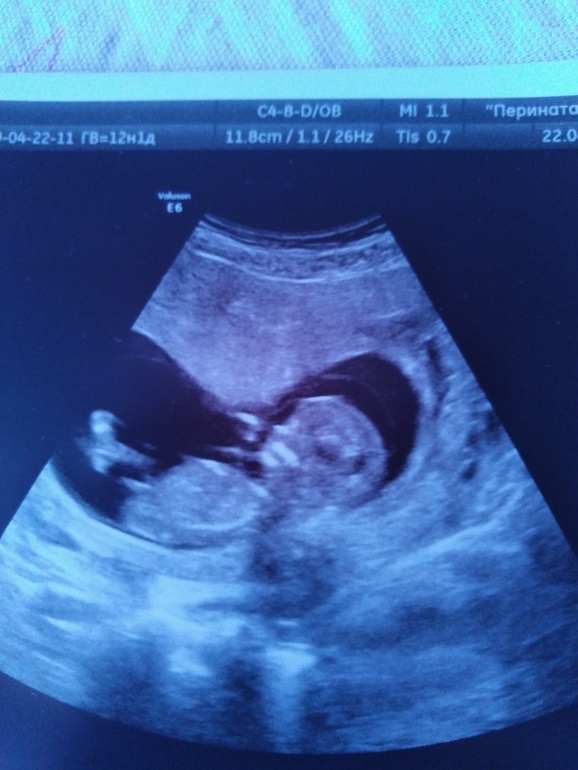

Мне на первом скрининге сами предложили пол посмотреть, а я думала, что еще совсем рано. Но они не ошиблись, потом два раза подтвердили, причем я сама никогда не прошу пол посмотреть, а в жк когда шейку смотрели в 16 недель, тоже пол сами сказали. Для сравнения, вот так у нас в 12 недель было

22.04.2019

девчулька по моему)))

Девочка, половой бугорок не торчит, а почти параллельно